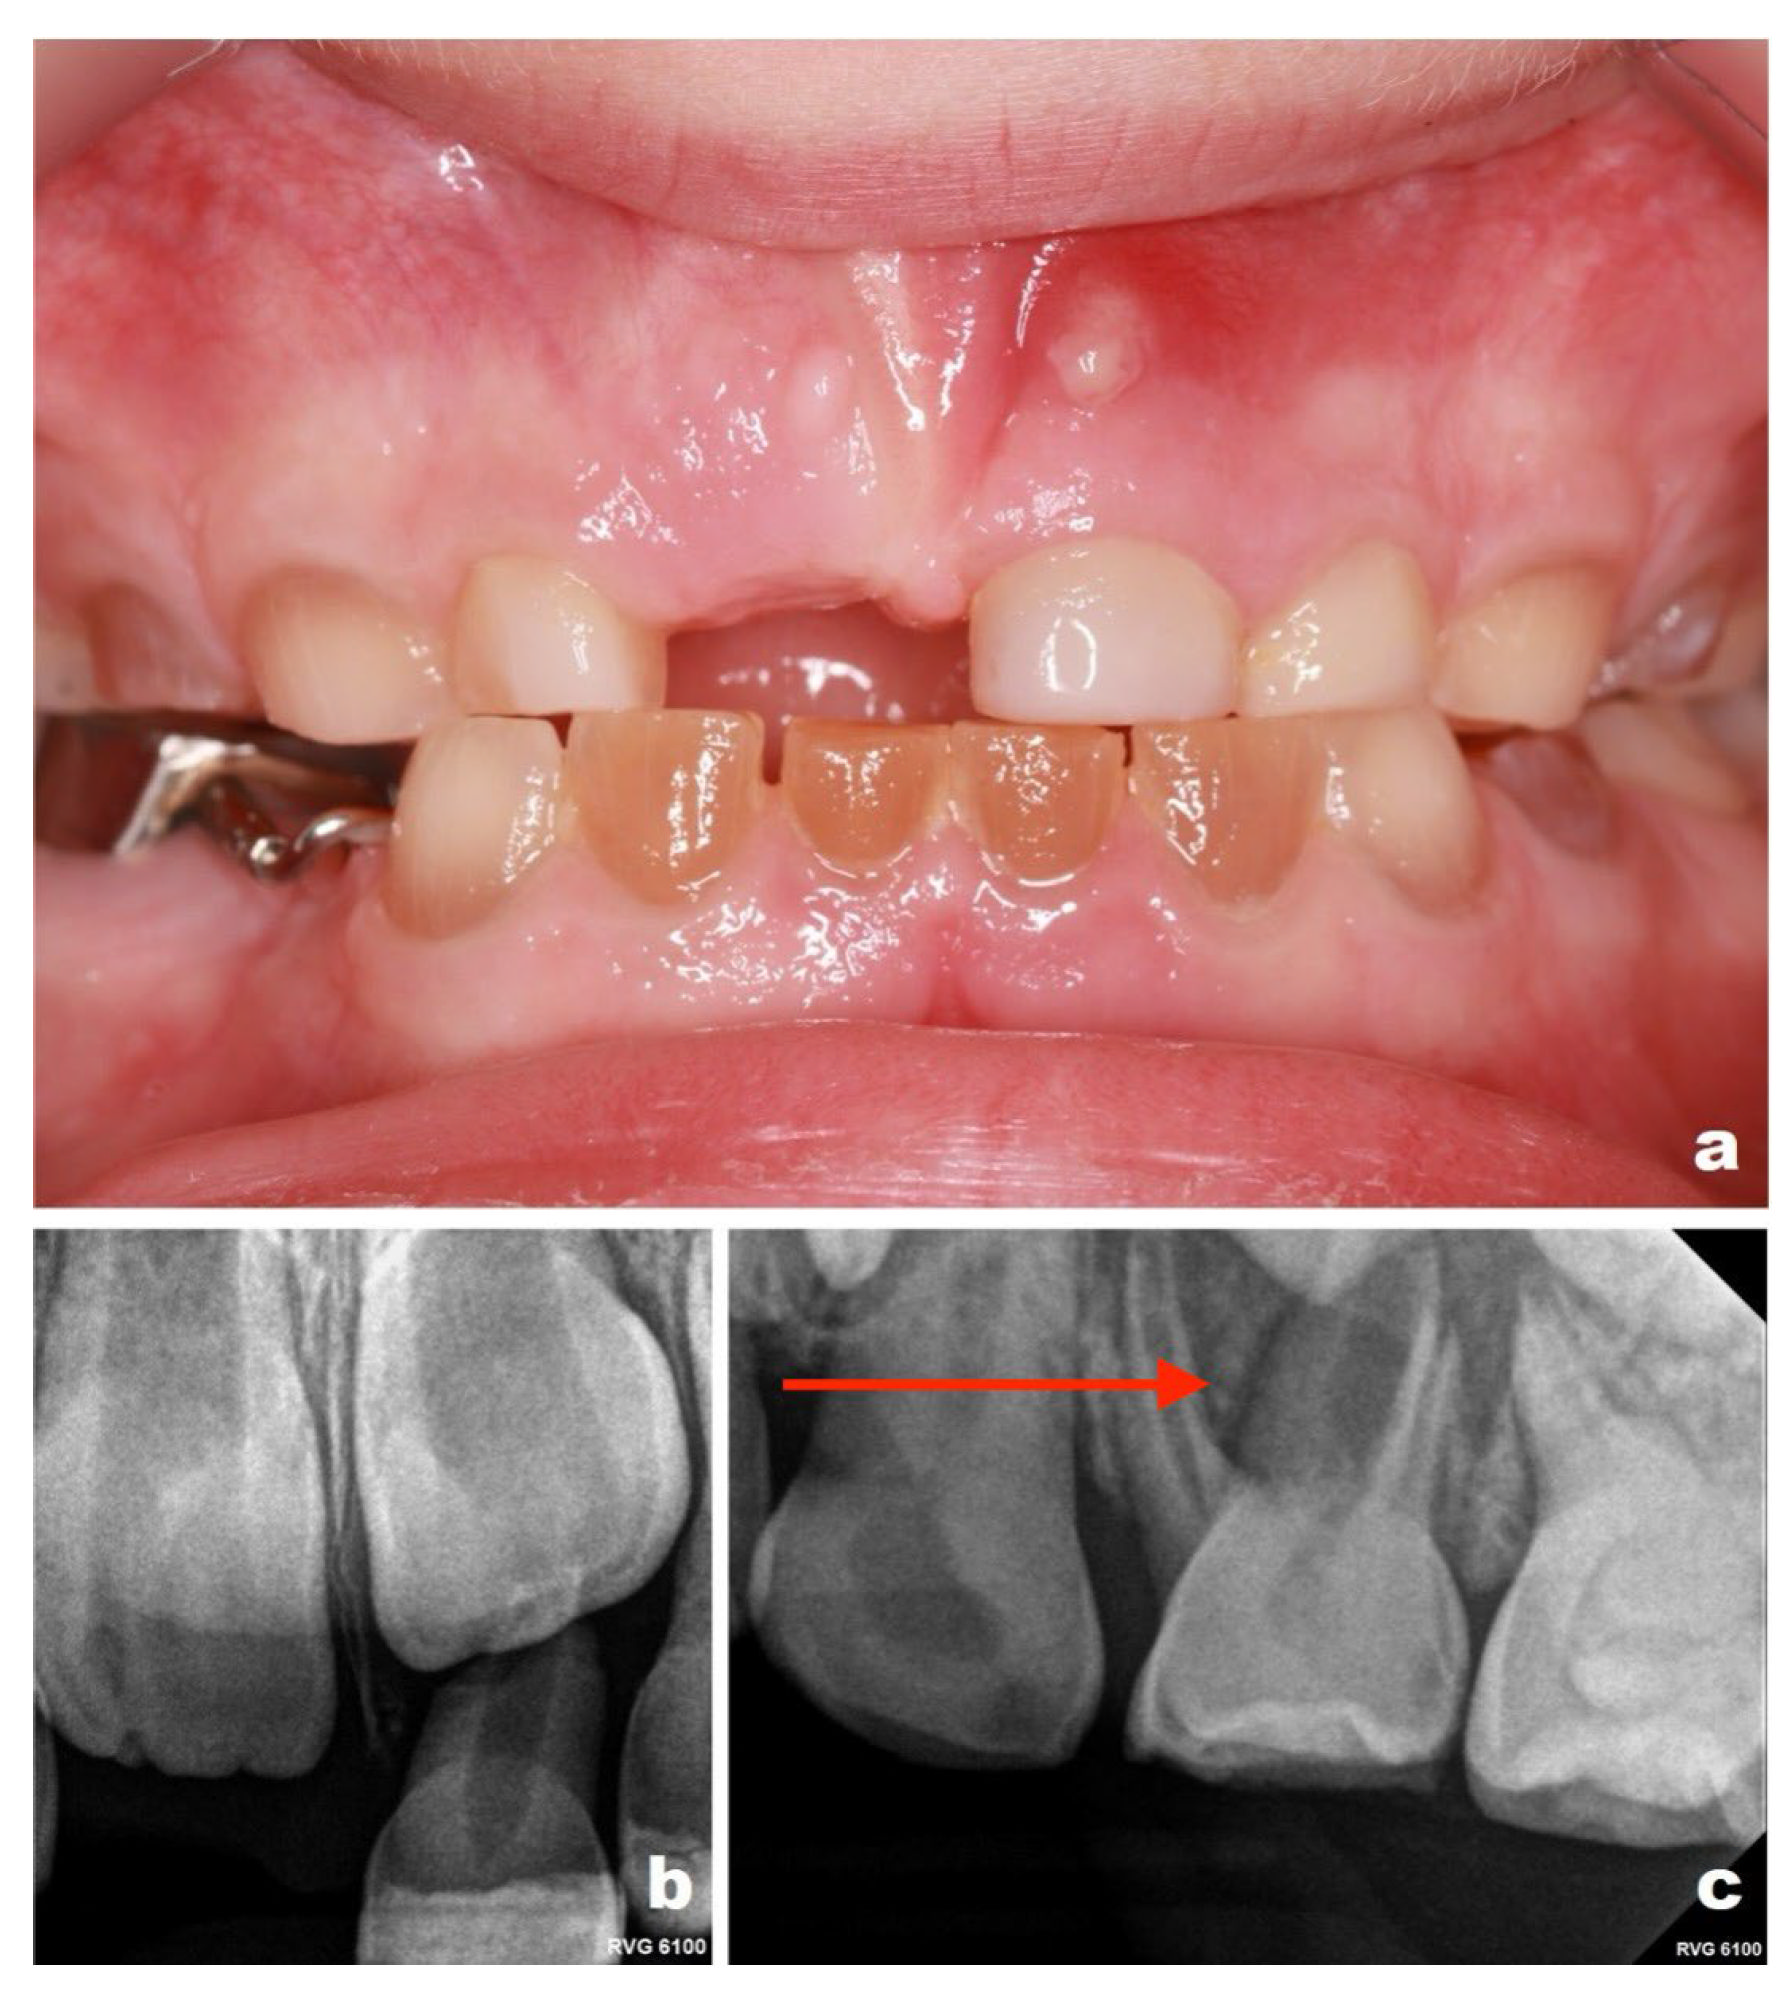

At a scheduled follow-up visit in January 2025, clinical examination revealed a sinus tract in the region of tooth 51. Periapical radiographs demonstrated pathological root resorption associated with tooth 84 and periapical inflammation related to tooth 51. Intraoral photographs were obtained to document these findings (Figure 4). While these findings indicate disease progression, it cannot be determined whether earlier restorative intervention would have altered the clinical course.

Given the radiographic evidence of infection, extractions of teeth 84 and 51 were performed to eliminate active pathology. A space maintainer was placed in the region of the extracted tooth 84 to preserve arch length. At a subsequent follow-up visit in September 2025, periapical radiographs revealed inflammatory changes associated with tooth 64 and a sinus tract in the region of tooth 61 (Figure 5). As tooth 64 remained clinically asymptomatic and close to exfoliation, extraction was deferred until eruption of tooth 26. In contrast, tooth 61 was extracted to control infection. These decisions were based on a combination of radiographic findings, clinical status, and expected timing of exfoliation, rather than symptoms alone.

Figure 4. Intraoral photographs and periapical radiographs obtained in January 2025 (patient aged 5 years): (a) clinical photograph showing a sinus tract adjacent to tooth 51; (b) periapical radiograph of tooth 51 demonstrating periapical inflammation and pathological widening of the root canal; (c) periapical radiograph of tooth 84 revealing periapical inflammation (Please note the area indicated by the red arrow in the figure).

Figure 5. Intraoral photographs and periapical radiographs obtained in September 2025 (patient aged 6 years): (a) clinical photograph showing a sinus tract adjacent to tooth 61; (b) periapical radiograph of tooth 61 demonstrating root resorption and proximity to the permanent successor; (c) periapical radiograph of tooth 64 revealing periapical inflammation (Please note the area indicated by the red arrow in the figure).